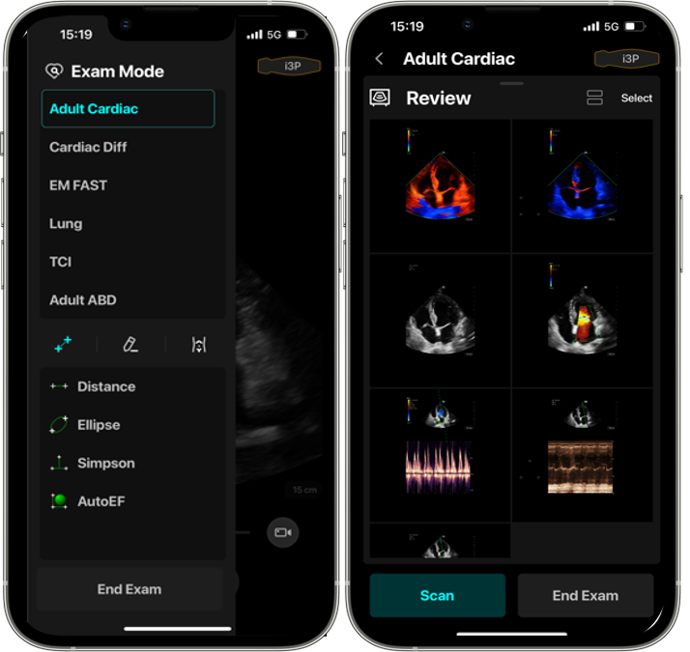

Приложение за мобилния телефон

Професионално приложение за мобилния телефон, което дава възможност да:

Правите измервания

Споделяте и коментирате изследвания

Въвеждате бележки и много други

Auto EF (опция)

Интелигентен начин за анализ на 2D ехо клипове за автоматично разпознаване на диастолa / систолa и изходни EDV / ESV / EF и др. Резултати чрез метода на Симпсън.